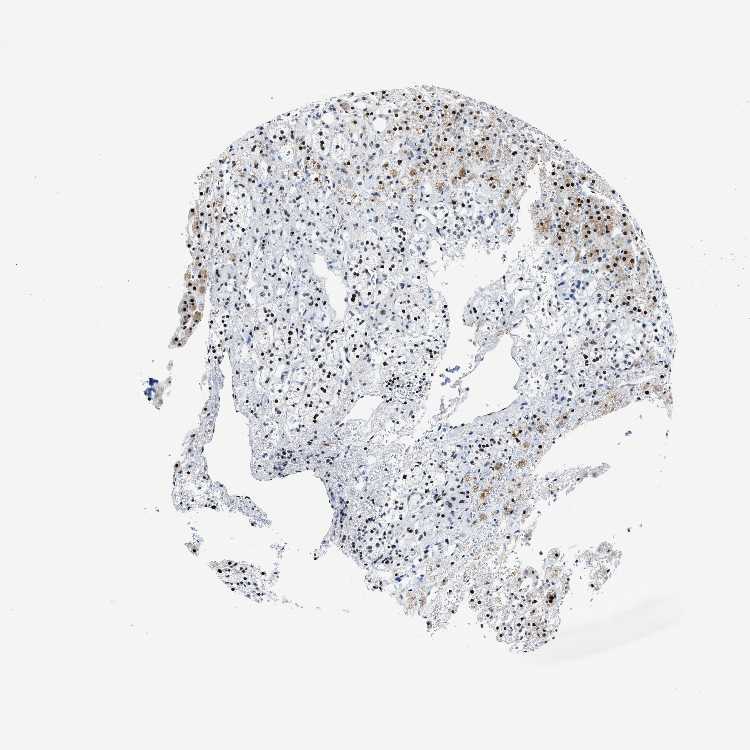

ADRENAL GLAND - Antibody stainingi

Antibody staining in the annotated cell types in the current human tissue is reported as not detected, low, medium, or high, based on conventional immunohistochemistry profiling in selected tissues. This score is based on the combination of the staining intensity and fraction of stained cells.

Each image is clickable and will lead to virtual microscopy that enables deeper exploration of all samples and also displays staining intensity scores, fraction scores and subcellular localization as well as patient and tissue information for each sample.

Antibody HPA020131

Glandular cells High